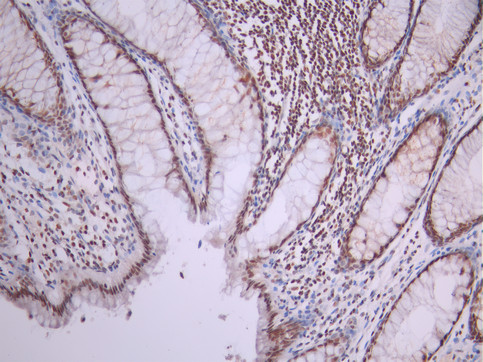

IHC image of CSB-RA049800A0HU diluted at 1:100 and staining in paraffin-embedded human colorectal cancer performed on a Leica BondTM system. After dewaxing and hydration, antigen retrieval was mediated by high pressure in a citrate buffer (pH 6.0). Section was blocked with 10% normal goat serum 30min at RT. Then primary antibody (1% BSA) was incubated at 4°C overnight. The primary is detected by a Goat anti-rabbit polymer IgG labeled by HRP and visualized using 0.05% DAB.